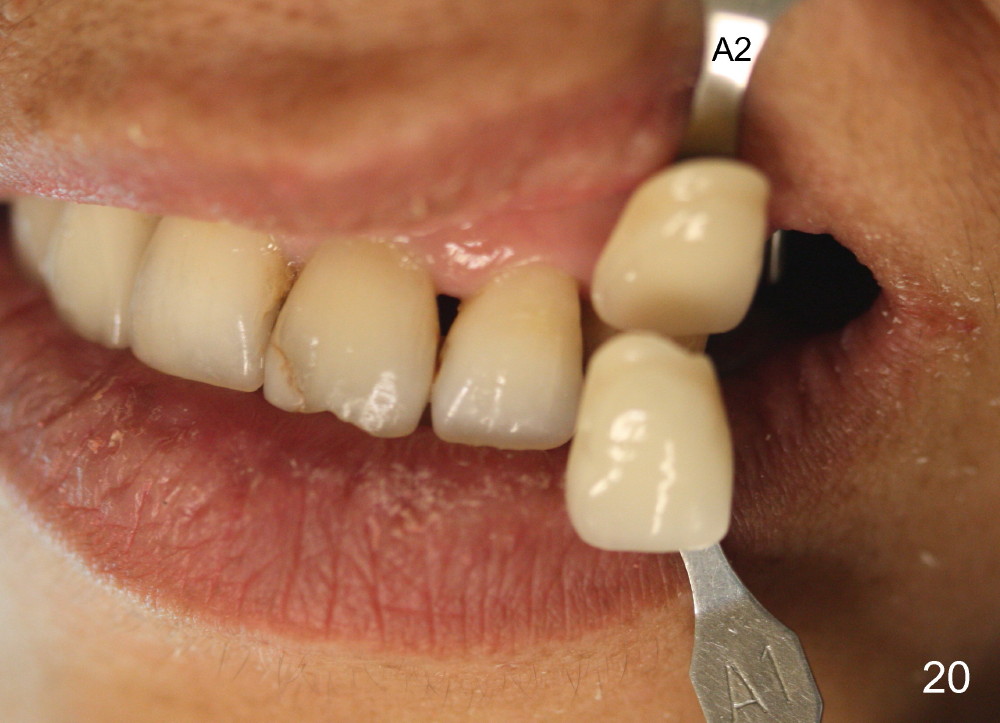

Two PAs are taken 5 months postop (Fig.15,16). Patterns of bone graft (*) between these PAs are different, which suggests presence of the graft buccal to the implant at the site of #14. Another piece of evidence of the graft is that the buccal socket heals (Fig.17 B) without implant thread exposure (Fig.19). These two implants are ready for definitive restoration (Fig.18-20). Fig.21 shows the final restoration 5 months post cementation.